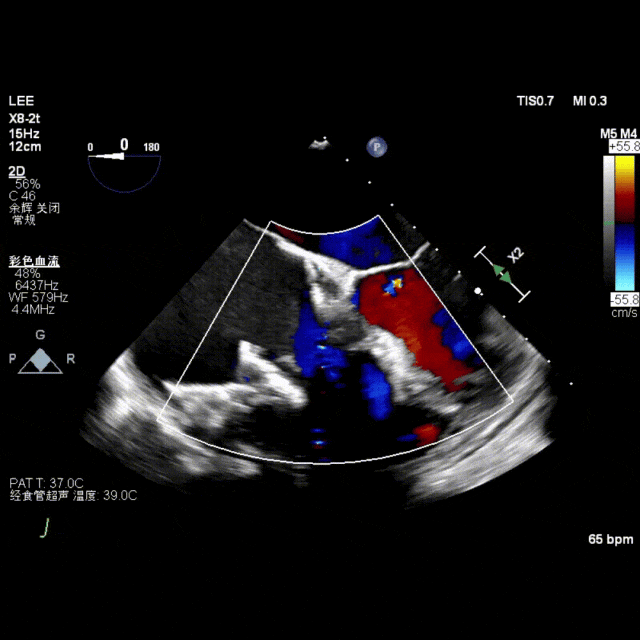

术前超声提示重度反流